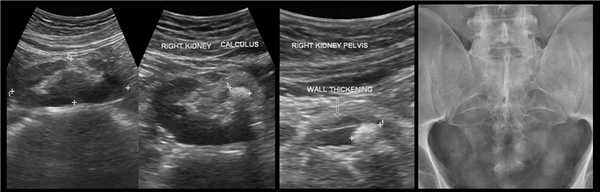

Рисунок. Пациент с острой почечной коликой. На УЗИ слева в дистальном отделе мочеточника гиперэхогенное округлое образование с акустической тенью (1), мочеточник расширен на всем протяжении (2), лоханка и большие чашечки умеренно расширены (3, 4). Заключение: Камень в дистальном отделе мочеточника. Вторичный мегоуретер и гидронефроз 2 степени.